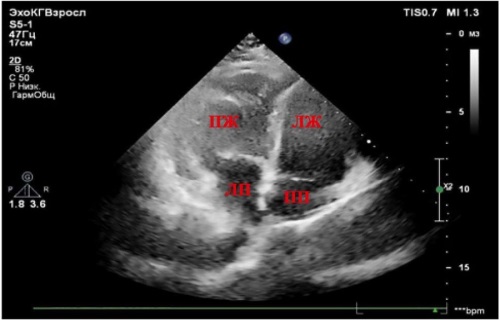

Левый желудочек закономерно является наиболее уязвимой структурой у больных с кардиальной патологией — артериальной гипертензией, ишемической болезнью сердца и их частым сочетанием в клинической практике. Особенности его структурно-функциональных нарушений в настоящее время хорошо изучены и положены в основу патогенетической терапии. На этом фоне правый желудочек исследован явно недостаточно в связи с существовавшими ранее методическими сложностями в оценке его состояния. В то же время установлено, что дисфункция и ремоделирование правого желудочка у больных с кардиальной патологией может быть причиной развития сердечно-сосудистых осложнений вплоть до фатальных. В последнее время с внедрением новых ультразвуковых технологий расширяются возможности для оценки состояния обоих желудочков у больных с сердечно-сосудистыми заболеваниями, что может в ближайшей перспективе способствовать уточнению их прогноза и повышению эффективности проводимой терапии.

В рамках публикации рассмотрен врождённый порок сердца — транспозиция магистральных сосудов, летальность при котором в первый месяц жизни составляет 50 %, в возрасте до года - 90 % случаев. Одним из вариантов транспозиции аорты и лёгочной артерии является корригированная транспозиция. В отечественной литературе описываются клинические случаи корригированной транспозиции магистральных сосудов в педиатрии, выявленные в первые месяцы и годы жизни ребенка. В статье представлен клинический случай корригированной транспозиции магистральных сосудов, впервые выявленной у пациентки в зрелом возрасте.